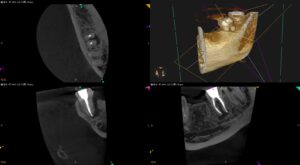

根尖病変があり、臨床症状のある歯の再根管治療〜#18 Re-RCT+Core build up

紹介患者さんの治療。 主訴は 左下奥歯の咬合痛。左側でものが噛めない… であった。 歯内療法学的検査(2023.10.17) #18 Cold N/A, Perc.(+), Palp.(-), BT(++), Perio … 続きを読む 根尖病変があり、臨床症状のある歯の再根管治療〜#18 Re-RCT+Core build up